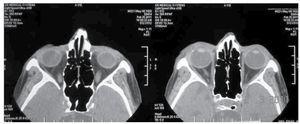

Se estableció como diagnóstico presuntivo carcinoma epidermoide invasor de la conjuntival, por lo que se solicitaron pruebas de ultrasonido y tomografía oculares. En la ecografía ocular se observó una lesión ocupativa nasal al cristalino, presentando en la ultrabiomicroscopia engrosamiento del iris en esa misma localización, membranas en cámara anterior y sinequias anteriores en el ángulo iridocorneal (Figura 2). En la tomografía presentaba captación de contraste en sector nasal del ángulo iridocorneal del ojo derecho sin afectación de párpados, órbita ni anexos oculares (Figura 3).

Figura 3. Tomografía contrastada, cortes axiales a nivel de la lesión.